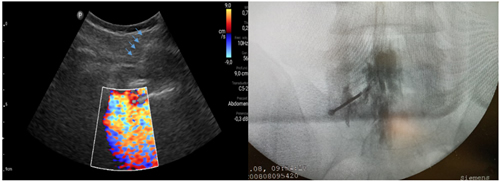

Los procedimientos fueron realizados en sala de operaciones, con vía venosa periférica y en posición decúbito ventral. Los mismos fueron realizados por el investigador principal (P. C.) con experiencia en la realización de procedimientos ecoguiados en la columna vertebral, utilizando la técnica paramediana en eje ecográfico corto. Se utilizó un ecógrafo portátil modelo Lumify marca Phillips, con transductor curvo de baja frecuencia. Fundas y gel ecográfico de la marca Pajunk® (Pajunk GmbH Medizintechnologie, Geisingen, Germany). En cada caso se identificó el espacio L4-L5 o L5-S1 mediante escaneo ecográfico de la columna lumbosacra en el plano transversal y longitudinal previo al inicio del procedimiento. Con la sonda ecográfica colocada en plano transversal o en eje corto, se realiza un habón anestésico 1 a 2 cm a un lado del transductor, correspondiente al lado del dolor radicular. La aguja de Tuohy ecogénica, 18 G (Tuohy Sono, 18G Pajunk® GmbH Medizintechnologie, Geisingen, Germany) de 9 o 12 cm según la contextura del paciente, se dirige en plano, en tiempo real, en sentido lateral a medial, entre la articulación facetaria por fuera y el ligamento interespinoso por dentro, hasta alcanzar el ligamento amarillo, en el espacio interlaminar elegido (Figura 1). El espacio epidural fue identificado mediante la pérdida de resistencia con suero fisiológico. Se registró la imagen doppler color durante la maniobra, como medida alternativa a la epidurografía con contraste (Figura 2). Posteriormente, 5 cc de contraste no iónico fue inyectado. Se consideró que fue alcanzado dicho espacio cuando el contraste se distribuye a lo largo del ligamento longitudinal posterior (Figura 2). 1 mg/kg de triamcinolona más 3 cc de lidocaína al 0,5 (hasta 10 cc de solución total) se inyectan en el espacio epidural.

Fig. 1. Escaneo ecográfico en eje corto o transversal del espacio L5-S1. La flecha amarilla muestra el punto de entrada de la aguja de Touhy en el abordaje paramedial y su trayecto. A la derecha se muestra la colocación de la aguja Sono Touhy en plano con el transductor curvo.

Fig. 2. Inyección de 5 a 10 ml de suero fisiológico con registro de la imagen doppler color, que se distribuye en el canal raquídeo, en una inyección epidural L5S1 paramediana derecha (imagen a la izquierda). Las flechas azules indican el trayecto de la aguja de Touhy. A la derecha se observa la confirmación con epidurograma de una inyección epidural L5S1 izquierda.